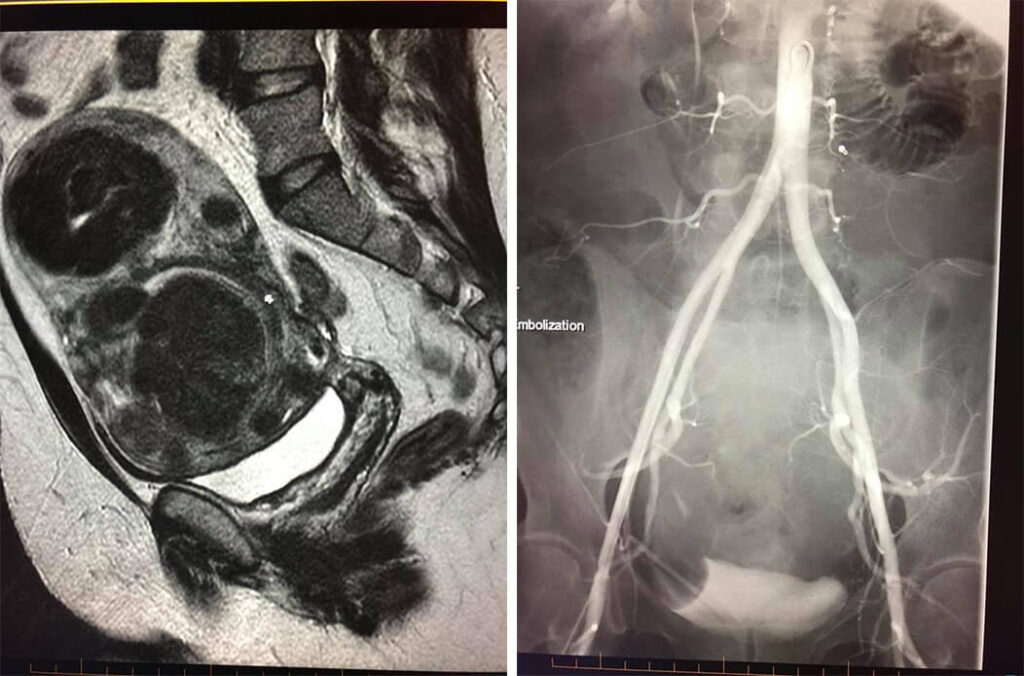

38 year old female with large fibroids in the uterus. Uterus is size of 6 month pregnancy. She complains of severe pain and irregular bleeding because of the fibroids. She elected to have an uterine artery embolization (also known as uterine fibroid embolization UAE/UFE) instead of surgery. We inserted a microcatheter into the uterine arteries and blocked off the blood supply to the fibroids with microspheres. 1 month later all her symptoms have resolved. 6 months later her fibroids have all shrunk or disappeared with no blood flow to the fibroids. And uterine function is normal!!